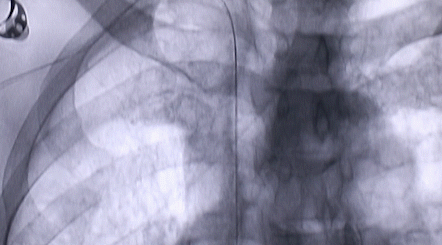

1月12日,西安國際醫(yī)學中心醫(yī)院心臟外科郭穎強主任團隊成功為一名腹主動脈閉塞、右側腎動脈閉塞、左側腎動脈重度狹窄、腹壁淺表動脈側支循環(huán)形成、高血壓病3級(極高危組)合并閉塞性周圍動脈粥樣硬化、急性腎功能不全的老年患者實施腎動脈球囊擴張 腎動脈支架植入術 動脈血栓抽吸術 髂動脈開通術,治好了困擾患者多年的頑固性高血壓?;颊吣壳翱祻土己?,將于近日出院。

按照術前制定的方案,郭穎強主任和楊金保博士首先嘗試開通閉塞的右腎動脈,但由于血栓機化、鈣化嚴重,右腎動脈難以開通。遂謹慎擴張狹窄的左腎動脈,并成功植入一枚支架。之后經(jīng)過反復旋磨、抽吸,順利開通髂動脈,但腹主動脈閉塞段仍難以擴通。此時,患者居高不下的血壓很快恢復到正常水平。